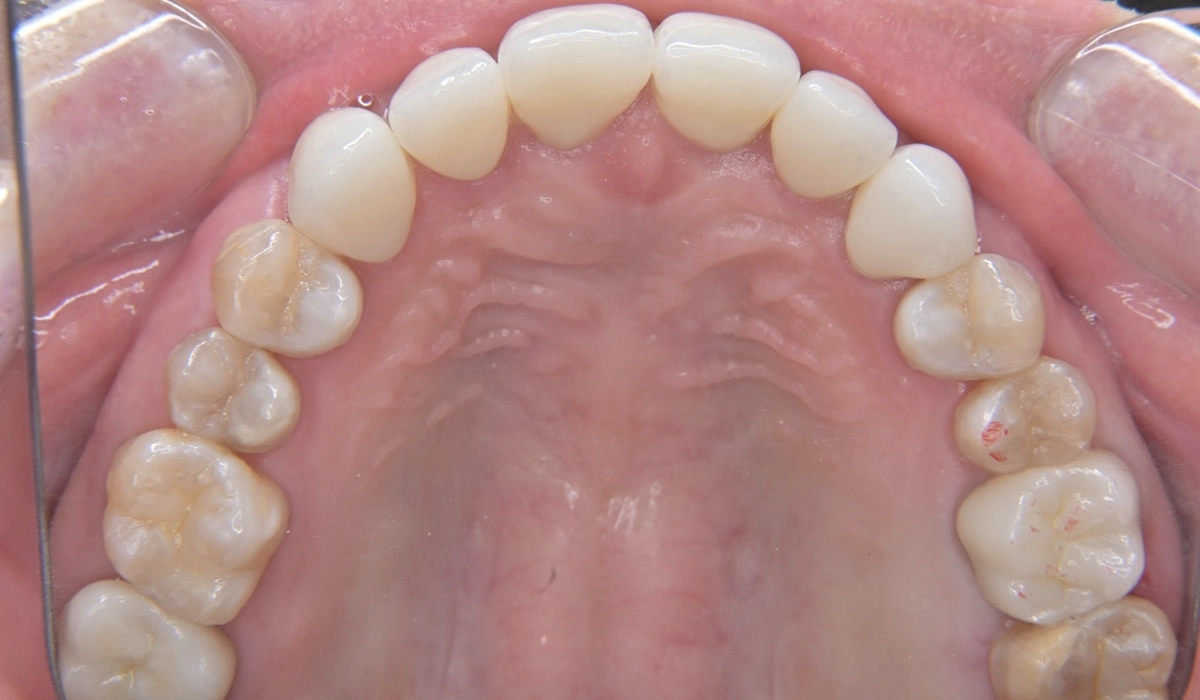

治療後の写真がこちらになります。

プロビジョナルレストレーションで問題点していたブラックトライアングルの問題が最終補綴物では修正できていることがわかります。

右上6と左下7はダイレクトボンディングにより必要最小限の切削介入で治療を行っています。右下6欠損部に対しては様々な治療選択肢のメリット・デメリットを考慮の上ジルコニアブリッジによる欠損修復治療を行いました。

本症例では術前に歯肉の形態や歯冠の最終形態を模型上で診査・診断をした上で治療を開始しました。審美的なゴールを設定しているため回り道をせずに一直線に思い描いていたゴールに到達することができました。

歯周環境については患者様とともに歯周基本治療により改善した状態を維持できており、今後も安定した歯周環境の維持に取り組みたいと考えています。